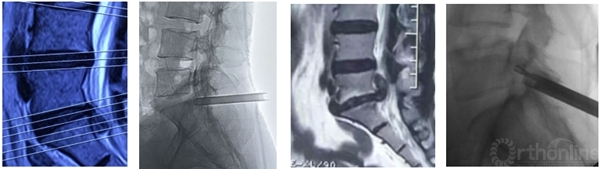

术前造影显示后纵韧带完整性,术中保护后纵韧带

脊柱内镜日间手术需进一步提高穿刺的精准性,避免反复穿刺。

靶向穿刺